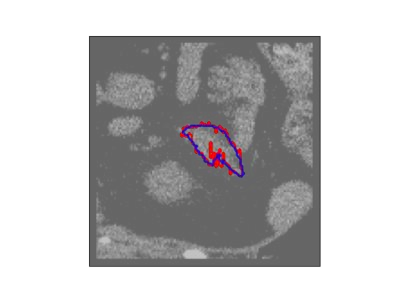

The human annotations are imperfect, especially when produced by junior practitioners. Multi-expert consensus is usually regarded as golden standard, while this annotation protocol is too expensive to implement in many real-world projects. In this study, we propose a method to refine human annotation, named Neural Annotation Refinement (NeAR). It is based on a learnable implicit function, which decodes a latent vector into represented shape. By integrating the appearance as an input of implicit functions, the appearance-aware NeAR fixes the annotation artefacts. Our method is demonstrated on the application of adrenal gland analysis. We first show that the NeAR can repair distorted golden standards on a public adrenal gland segmentation dataset. Besides, we develop a new Adrenal gLand ANalysis (ALAN) dataset with the proposed NeAR, where each case consists of a 3D shape of adrenal gland and its diagnosis label (normal vs. abnormal) assigned by experts. We show that models trained on the shapes repaired by the NeAR can diagnose adrenal glands better than the original ones. The ALAN dataset will be open-source, with 1,594 shapes for adrenal gland diagnosis, which serves as a new benchmark for medical shape analysis. Code and dataset are available at https://github.com/M3DV/NeAR.